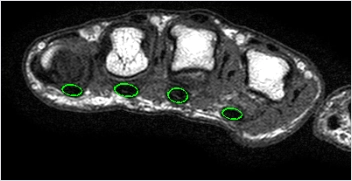

因手術上之需求及骨科微創技術的提倡,本團隊設計一套適用於扳機指微創手術之刀具組,除可利用微創概念及特殊設計之手術刀具器械解決臨床治療成效不好的問題外,亦可提供由特殊刀具完整切除之環狀腱鞘,進行組織學探討及醫學影像分析,並藉由生物力學及手部功能性評估病患的長期預後追蹤,對病程較為嚴重之病患探討其復健介入之成效。另外,本團隊運用人類手部屍體樣本以力學及材料特性之觀點,探討手指環狀腱鞘與屈指肌腱之特性,並與臨床評估及影像分析的研究結果連結整合,做病因學的探索,以協助未來臨床上的診斷及介入。本團隊亦透過研究前期所得之力學、影像及臨床參數,建立手部生物力學模型以供未來手部研究之用,並開發一套「整合性扳機指經皮解離手術模擬訓練系統」,架構出虛擬手術訓練系統,藉此訓練系統讓更多外科醫師練習並熟悉微創手術技術之操作,促進臨床醫療品質。